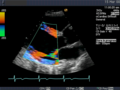

Die Aussagekraft der Sonografie kann erheblich durch die Anwendung des Doppler-Effekts erhöht werden. Man unterscheidet eindimensionale Verfahren (Pulsed-Wave-Doppler, Continuous-Wave-Doppler, auch als D-mode bezeichnet) von zweidimensionalen, farbkodierten Anwendungen (Farbdoppler – F-mode). Die Kombination B-Bild mit Pulsed-Wave-Doppler (PW-Doppler) nennt man auch Duplex.[4]

Doppler-Verfahren werden benutzt zur Bestimmung von Blutfluss-Geschwindigkeiten, zur Entdeckung und Beurteilung von Herz(klappen)fehlern, Verengungen (Stenosen), Verschlüssen oder Kurzschlussverbindungen (Shunts).

Bei der farbkodierten Doppler-Sonografie wird für einen großen Bereich eines konventionellen Ultraschallbildes (Color-Window) die örtliche Doppler-Frequenz (= mittlere Flussgeschwindigkeit) und deren Schwankungsbreite bestimmt. Damit möchte man die Turbulenz der Strömung abschätzen. Aufgrund der statistischen Bewegungen der Streuteilchen ist die Schwankungsbreite der Fließgeschwindigkeit jedoch stets größer als die Turbulenz. Das Ergebnis wird in Falschfarben auf dem B-Bild überlagert, also in Farbtönen von rot und blau für verschiedene Blutgeschwindigkeit und grün für Turbulenz. Hierbei steht üblicherweise die Farbe Rot für Bewegung auf den Schallkopf zu, während mit blauen Farbtönen Flüsse weg von der Sonde codiert werden. Bereiche der Geschwindigkeit 0 werden durch die Elektronik unterdrückt.

Anwendung des Doppler-Verfahrens bei einer Herzuntersuchung: Mitralklappeninsuffizienz

Farb-Doppler und PW-Doppler. Innerhalb der Stenose ist wegen der hohen Flussgeschwindigkeit und des resultierenden Alias-Effekts die Geschwindigkeit in Blau kodiert.